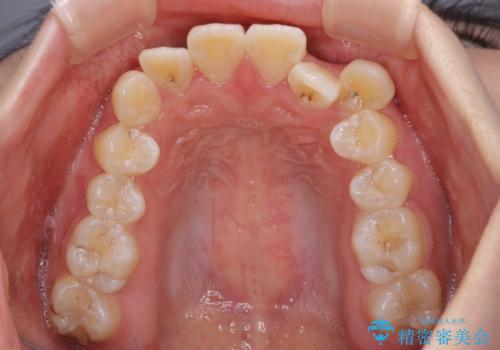

- 前歯のデコボコと八重歯を気にして来院された患者様です。

インビザラインでの治療を希望されていましたが、前歯のクロスバイトや下顎小臼歯の捻転が認められたため、インビザライン単独で治療を行うよりも、ワイヤー装置を併用した方が、治療期間の短縮やトラブル回避できると判断し、ワイヤー装置を併用することとしました。

まずはワイヤー装置により前歯のクロスバイトと下顎小臼歯の捻転を改善し、その後インビザラインにより全体を整える矯正治療を行うこととしました。

前歯のクロスバイトは、インビザラインでの改善中に前歯に過剰な力がかかり、歯髄壊死や歯肉退縮を引き起こすことがあります。また下顎小臼歯は寸胴型のため、捻転を排除することが難しいことが知られています。